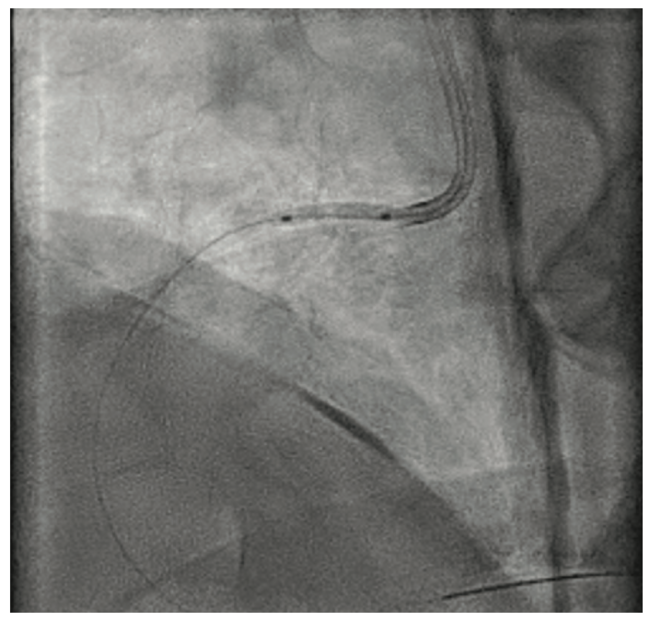

We proceeded with intervention to the RCA via right radial access using a 6 French (Fr) Terumo Glidesheath. Due to the critical ostial stenosis, a Terumo Runthrough wire was loaded in a 6 Fr Judkins right (JR)4 guide. There was severe pressure dampening on guide engagement and the wire was quickly advanced into the distal RCA. We attempted to deliver 2.5 and 2.0 mm Takeru semi-compliant balloons, but the balloons would not cross the proximal RCA stenoses. We then used a 1.5 mm Takeru semi-compliant balloon and dilated the ostial and proximal RCA, followed by 2.0 and 2.5 mm noncompliant balloons at 14 atmospheres (atm) (Figure 2). The ostial lesion was further dilated with a 2.5 x 10 mm Wolverine cutting balloon (Boston Scientific) at 8 atm. Intravascular ultrasound (IVUS) was performed with a Refinity catheter (Philips) (Figure 3A), and using a 6 Fr Guideliner (Teleflex), 2.5 mm x 38 mm and 2.5 mm x 22 mm Onyx Frontier drug-eluting stents (Medtronic) were deployed from the ostium to the mid RCA at 12 atm. The stents were post dilated with 3.0 and 3.5 mm Takeru noncompliant balloons at 18 atm. There was an excellent angiographic result with no residual stenosis (Figure 4A). IVUS showed well-expanded and well-apposed stents without evidence of dissection (Figure 3B), and the ostial RCA minimal stent area was 10mm2. The entire intervention was performed with only 65 mL of contrast dye. The patient was maintained on dual antiplatelet therapy with aspirin 81 mg and clopidogrel 75 mg daily. The patient returned for staged intervention to the LAD with rotational atherectomy and intravascular lithotripsy (Shockwave Medical) (Figure 4B).